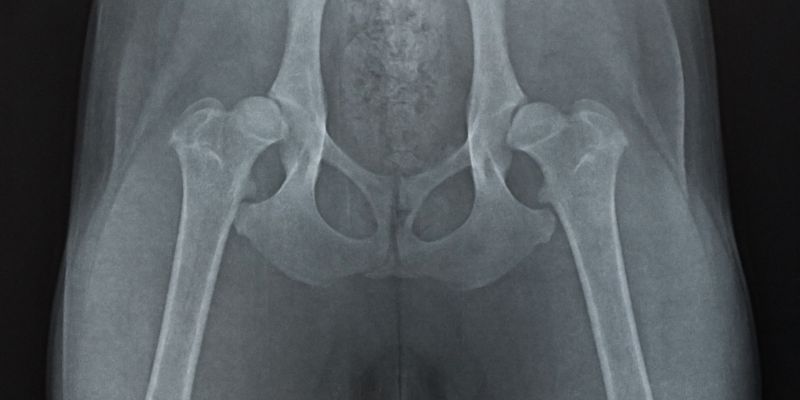

Diagnosen av höftdysplasi hos bebisar görs vanligtvis med hjälp av ultraljud och röntgen. Dessa undersökningar kan visa om höftleden är normal eller om det finns tecken på höftdysplasi. Enligt specialister är det viktigt att göra en tidig diagnos för att kunna ge rätt behandling.

- Radiologiska undersökningar: Radiologiska undersökningar som röntgen eller MRT kan visa abnormaliteter i höftleden.

- Röntgenundersökning för att diagnostisera och övervaka tillståndet